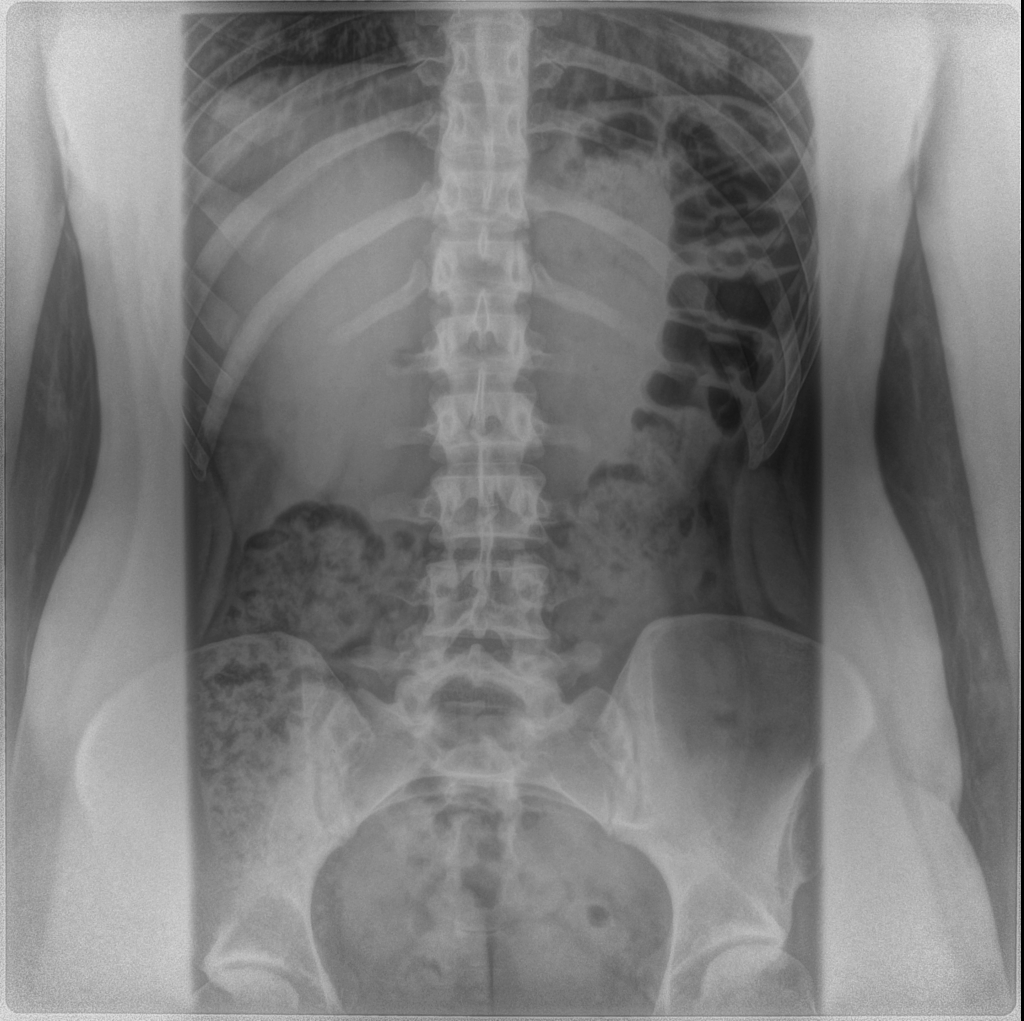

![]() |

| Note the asymmetry in the pelvis in the x-ray above. This will pull the ITB tight on one side, leading to unilateral ITB syndrome. |